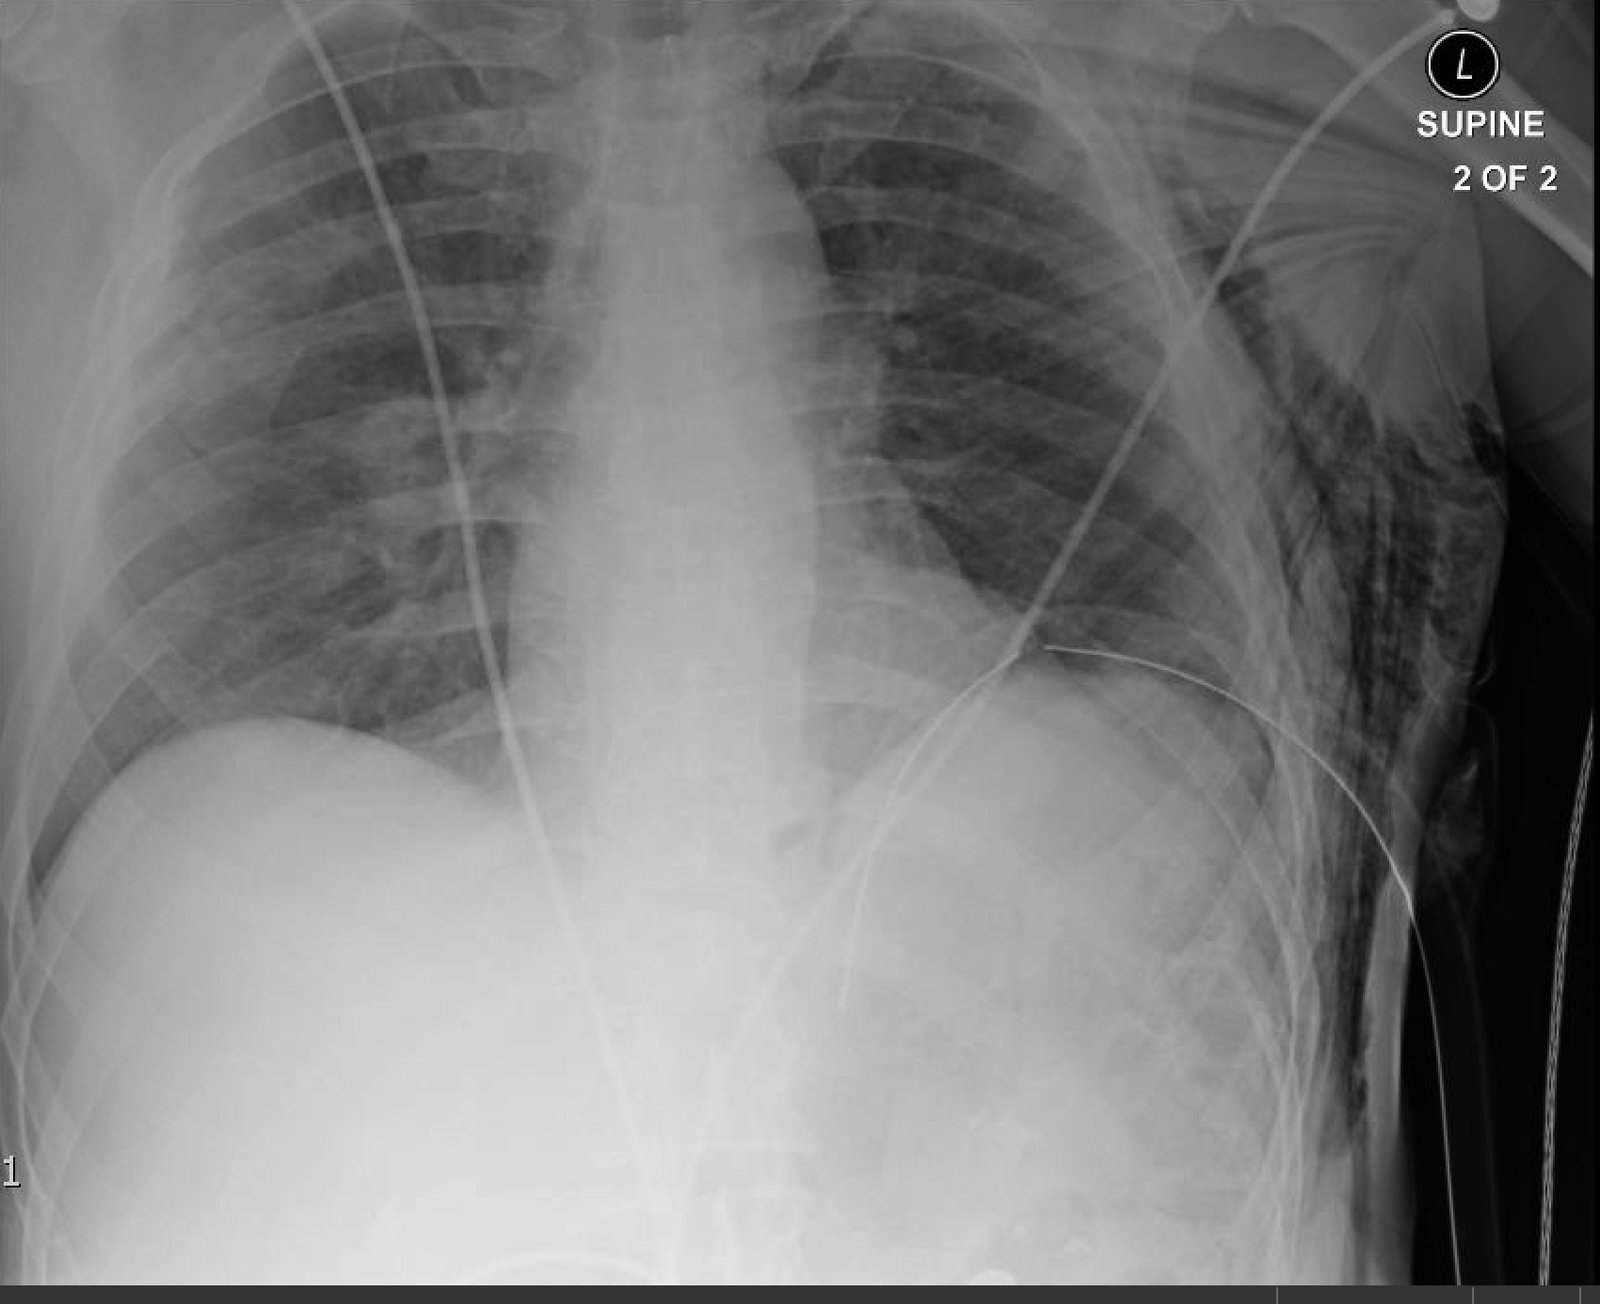

Plain film anteroposterior (AP) radiography of the chest shows left-sided subcutaneous emphysema (red arrow) with overlapping muscle striations of the pectoralis major (green arrow). After chest tube placement (blue arrow), AP chest radiography shows persistent left-sided subcutaneous emphysema (red arrow). CT of the chest shows pneumomediastinum (blue arrow), left apical pneumothorax (pink arrow), and subcutaneous emphysema (red arrow) at the level of T2. At the level of T6, rib fractures can be visualized on the CT (yellow arrow). At the level of T8, left sided pneumothorax is also seen (pink arrow) as the absence of lung tissue on CT.

Injuries of the thorax account for 25% of all mortality in trauma patients, of which many are preventable deaths by simple interventions.1,2 One sign commonly seen in patients with chest trauma is subcutaneous emphysema. The presence of this underlying emphysema has been suggested to be a sign of injury to the respiratory tract, making it clinically significant.3,4 Specifically, subcutaneous emphysema has been shown to be a clinical predictor of occult pneumothorax, with an odds ratio of 5.47.3 Furthermore, these injuries to the respiratory tract (pneumothorax /hemothorax, pneumomediastinum, etc.) can lead to hemodynamic instability and respiratory failure.4-6

In this patient, given the findings of multiple bilateral rib fractures, bilateral hemothorax/pneumothorax and multiple spine fractures, bilateral chest tubes were placed which had immediate output. The patient was admitted to surgical intensive care unit for chest tube management, pulmonary hygiene and further management of his other injuries.